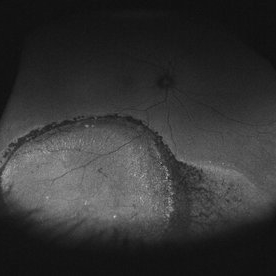

Fundus autofluorescence of a chronic inferior retinal detachment.

Condition/keywords: fundus autofluorescence (FAF)